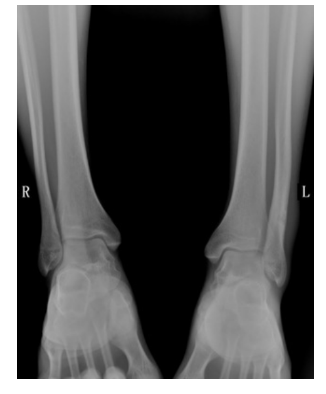

X线片检查

- 常规行正位、侧位、踝穴位

- 特殊位置:节内旋位、内斜位

- 应力位:前抽屉应力、距骨倾斜应力